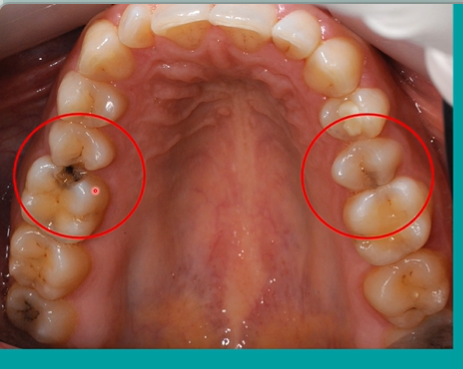

spot the caries

lower right and left second molars

are they the same colour? - the lower right has a fissure sealant

black one indicates staining and possible caries

compare the distal aspect of the upper 5s and the mesial aspects of the upper 6s - what can you see?

in the black - areas within the lesion there are still areas of remineralisation